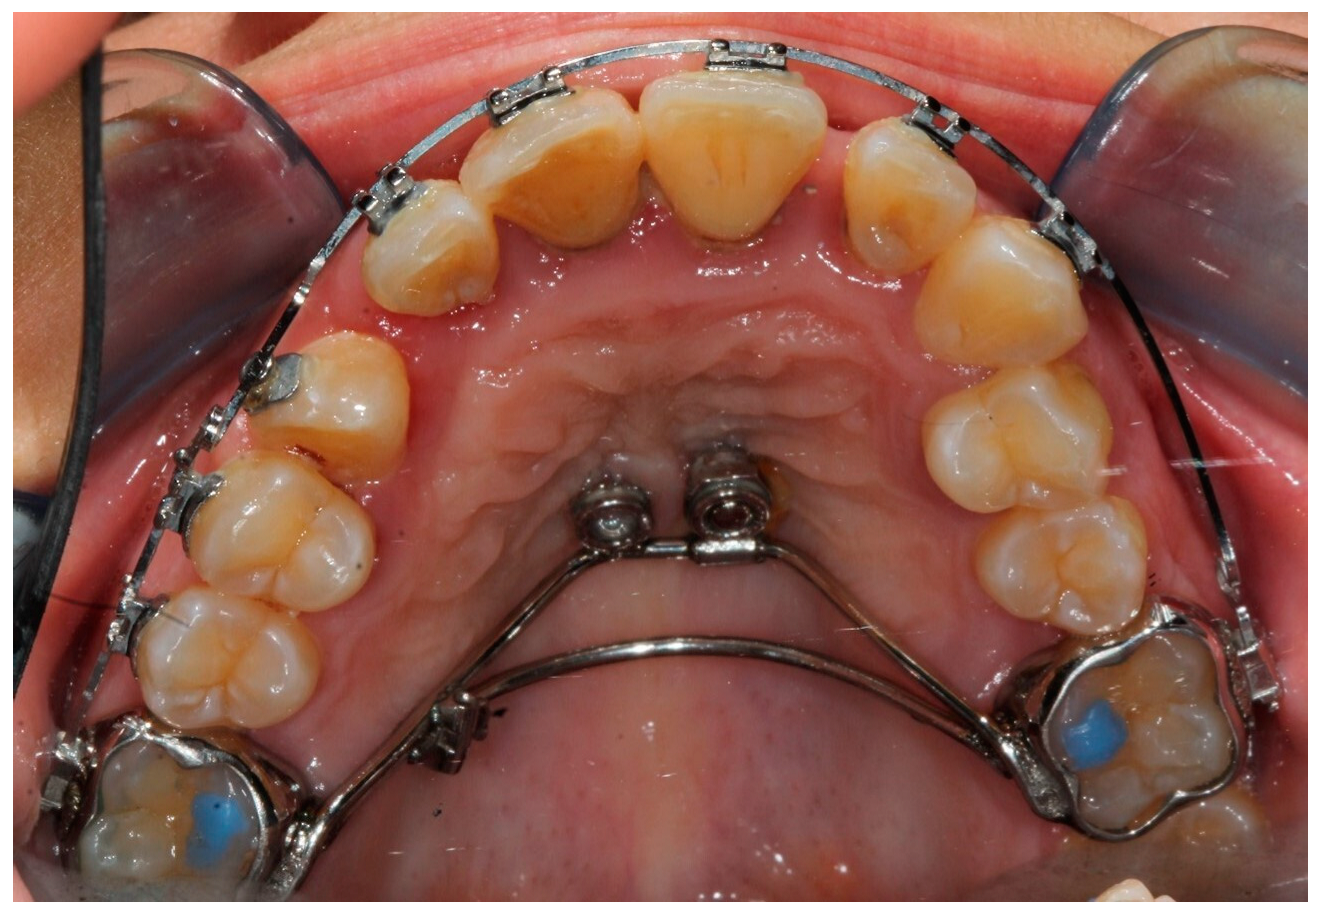

2. Case Report